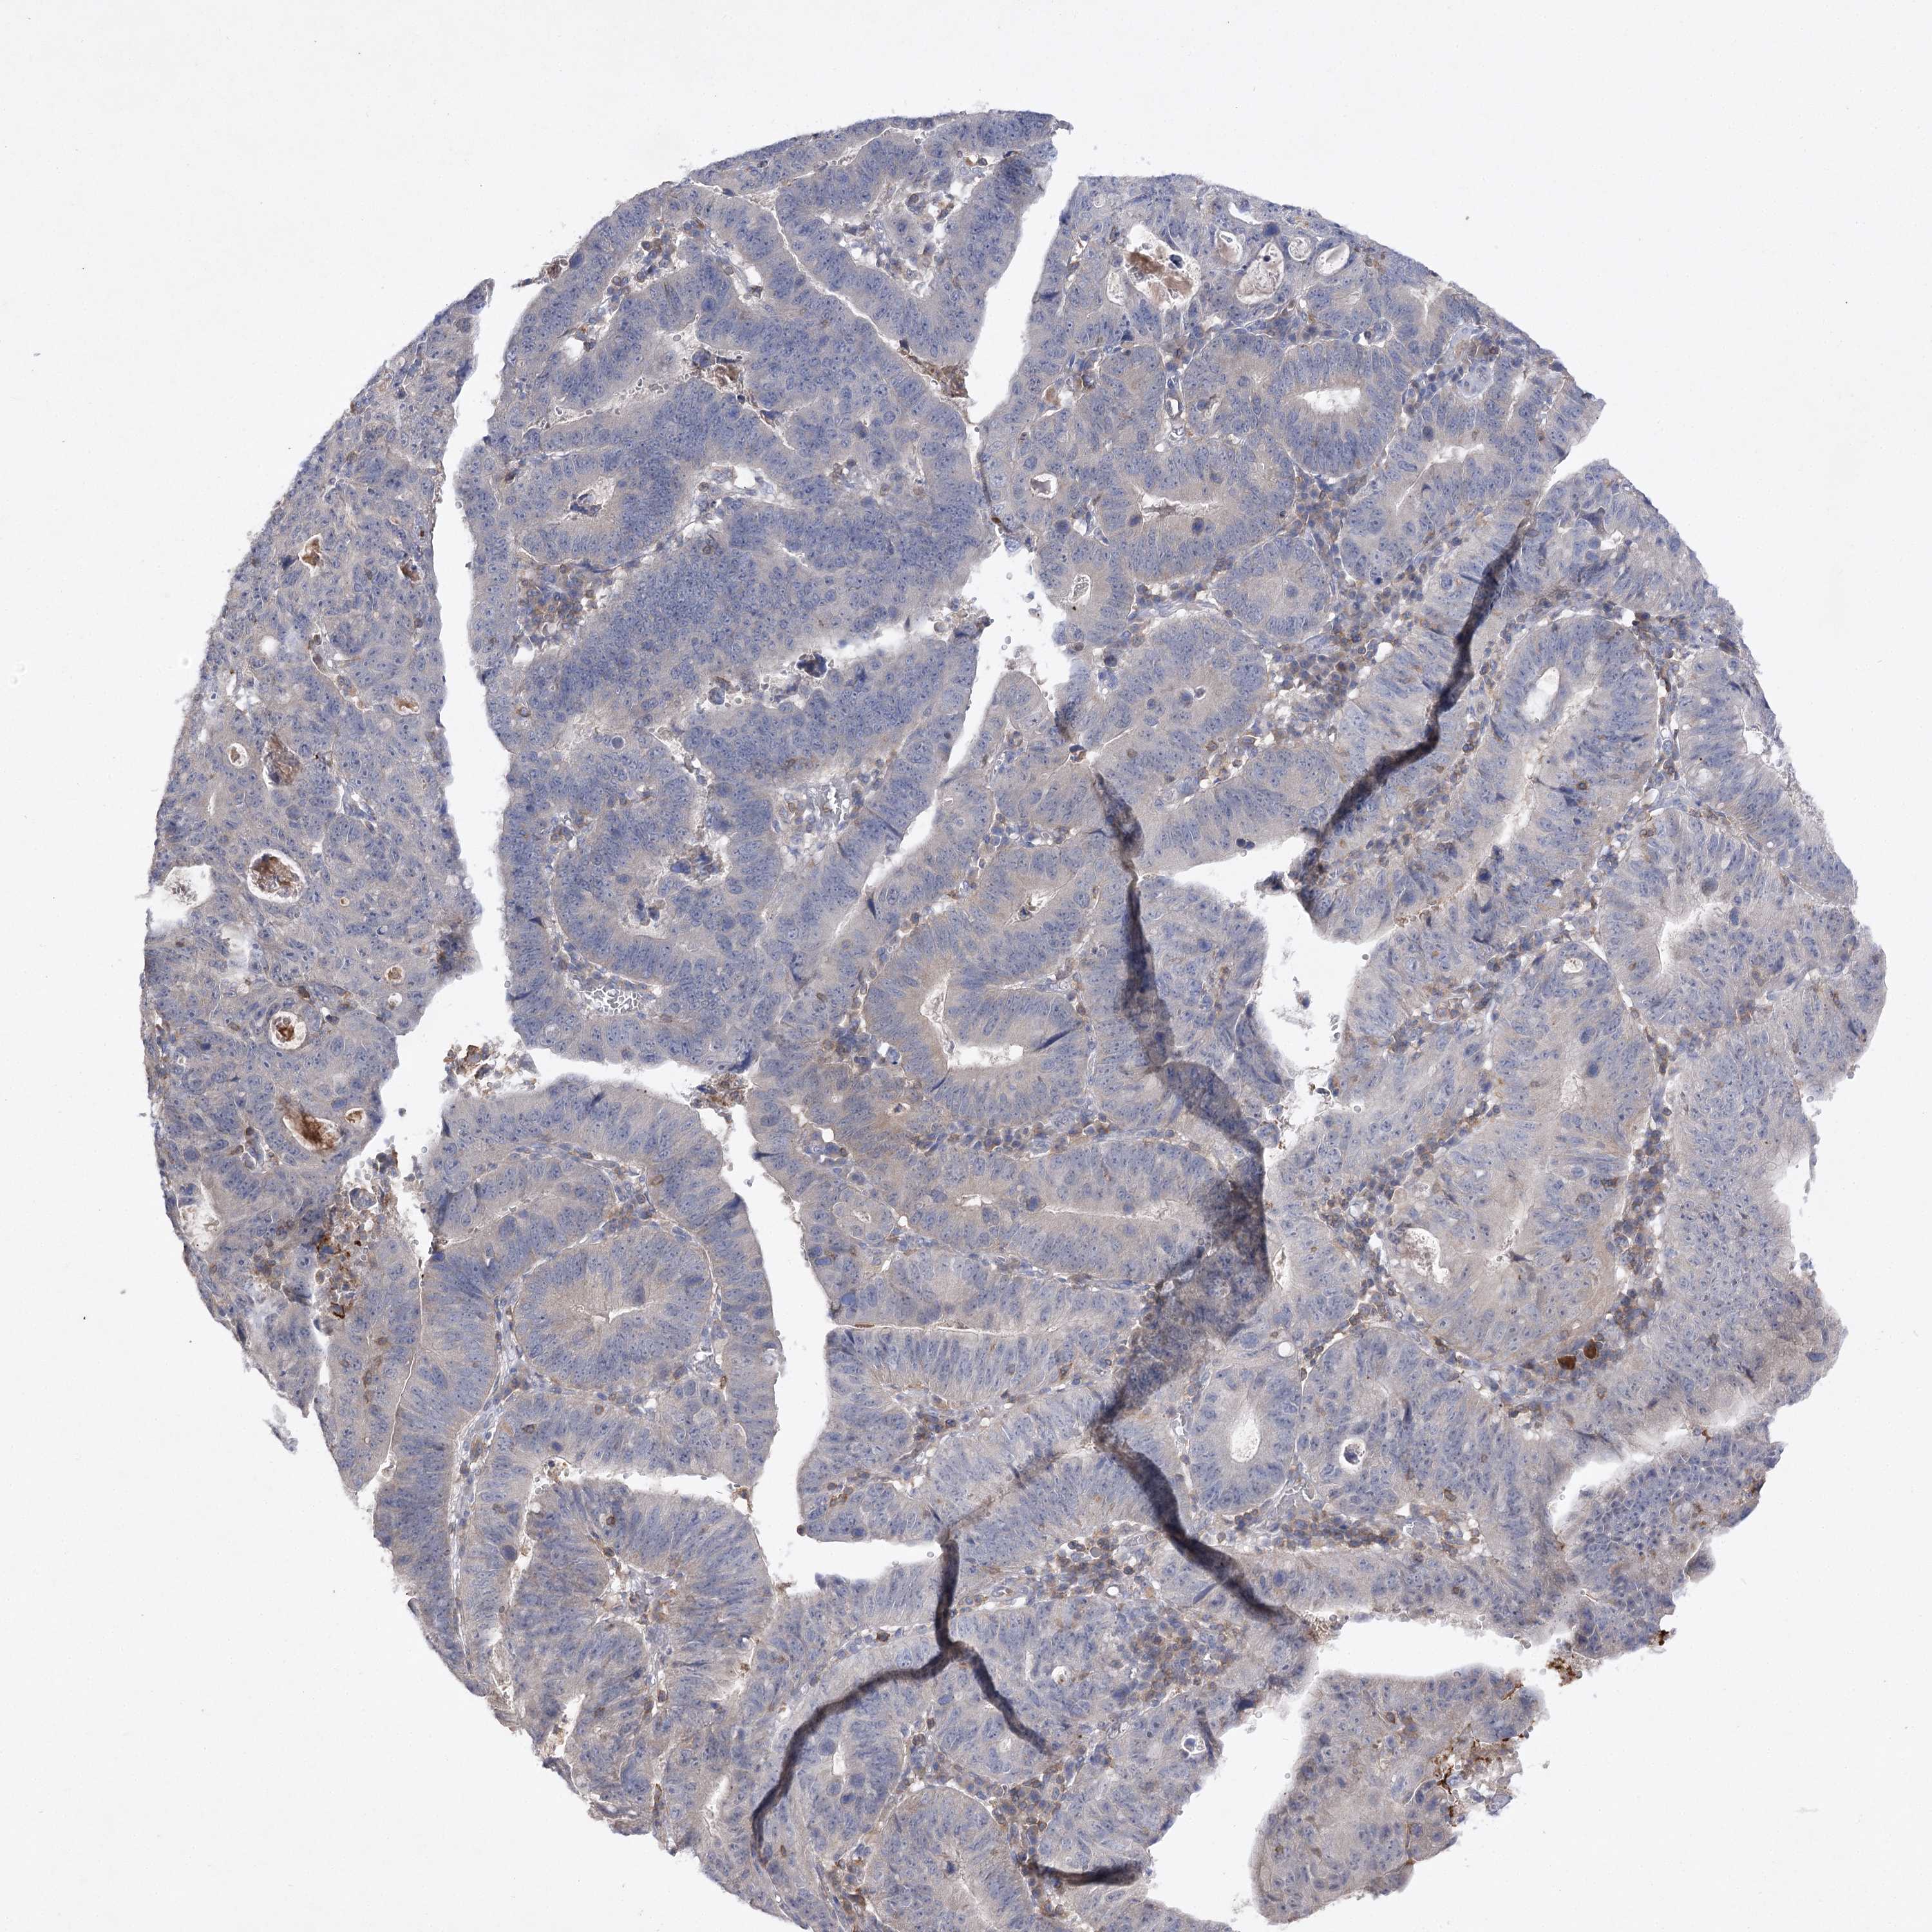

STOMACH CANCER - Protein expressioni

A mouse-over function shows sample information and annotation data. Click on an image to view it in a full screen mode. Samples can be filtered based on level of antibody staining by selecting one or several of the following categories: high, medium, low and not detected. The assay and annotation is described here.

Note that samples used for immunohistochemistry by the Human Protein Atlas do not correspond to samples in the TCGA dataset.

Antibody stainingi

Antibody staining in the annotated cell types in the current human tissue is reported as not detected, low, medium, or high, based on conventional immunohistochemistry profiling in selected tissues. This score is based on the combination of the staining intensity and fraction of stained cells.

Each image is clickable and will lead to virtual microscopy that enables deeper exploration of all samples and also displays staining intensity scores, fraction scores and subcellular localization as well as patient and tissue information for each sample.

Antibody HPA038337

Antibody CAB010421

Antibody CAB018545

Staining

High

Medium

Low

Not detected

Intensity

Strong

Moderate

Weak

Negative

Quantity

>75%

75%-25%

<25%

None

Location

Nuclear

Cytoplasmic/membranous

Cytoplasmic/membranous,nuclear

Adenocarcinoma, NOS